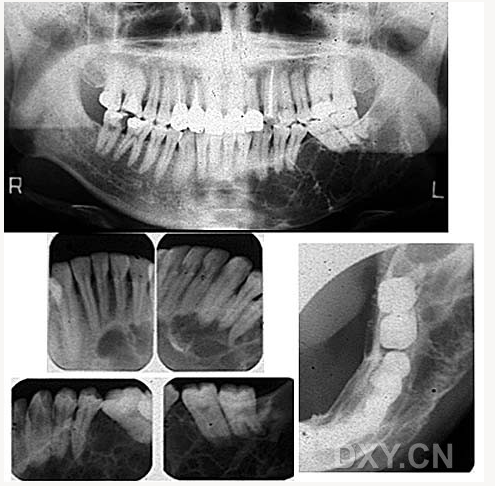

成釉細胞瘤

球狀上頜囊腫

含牙囊腫

球狀上頜囊腫    含牙囊腫

骨髓炎